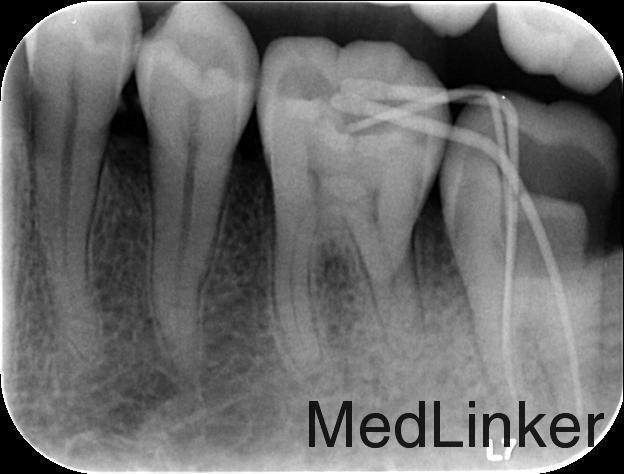

诊断:1、38近中阻生 2、37慢性牙髓炎 治疗计划:1、拔除38阻生齿 2、37根管治疗后冠修复 治疗:1. 37利多卡因局麻下,去腐未净露髓,暴露髓腔,降牙合,探及MB、ML、D三个根管口,置非砷慢失活剂,氧化锌水门汀暂封。嘱勿用患牙咬物。 38利多卡因局麻下分龈,去除近中阻力,挺松,拔除,搔刮牙槽窝,复位,局部压迫止血。 2.主诉:左下后牙上次治疗后无不适。 检查:37暂封物在,叩痛(—),牙体无松动,牙龈无明显红肿。 处置:37去除暂封物,拔残髓,10号C锉疏通根管,干燥根管,电测工作长度WL:MB=ML=18mm,D=18.5mm。EDTA下,常规预备至35#,3%过氧化氢和生理盐水冲洗+超声荡洗根管交替进行。隔湿,干燥根管,封CP棉球, 氧化锌水门汀暂封。嘱勿用患牙咬物。 3.主诉:左下后牙上次治疗后无不适。 检查:37暂封物在,叩痛(—),牙体无松动,牙龈无明显红肿。 处置:37去除暂封物,取出棉球,生理盐水冲洗并干燥根管,复测工作长度同前:MB=ML=18mm,D=18.5mm。进口根充糊剂+牙胶尖冷侧压根管充填,氧化锌水门汀暂封,术后拍片示:37根充恰填。嘱勿用患牙咬物。 建议:37桩冠修复